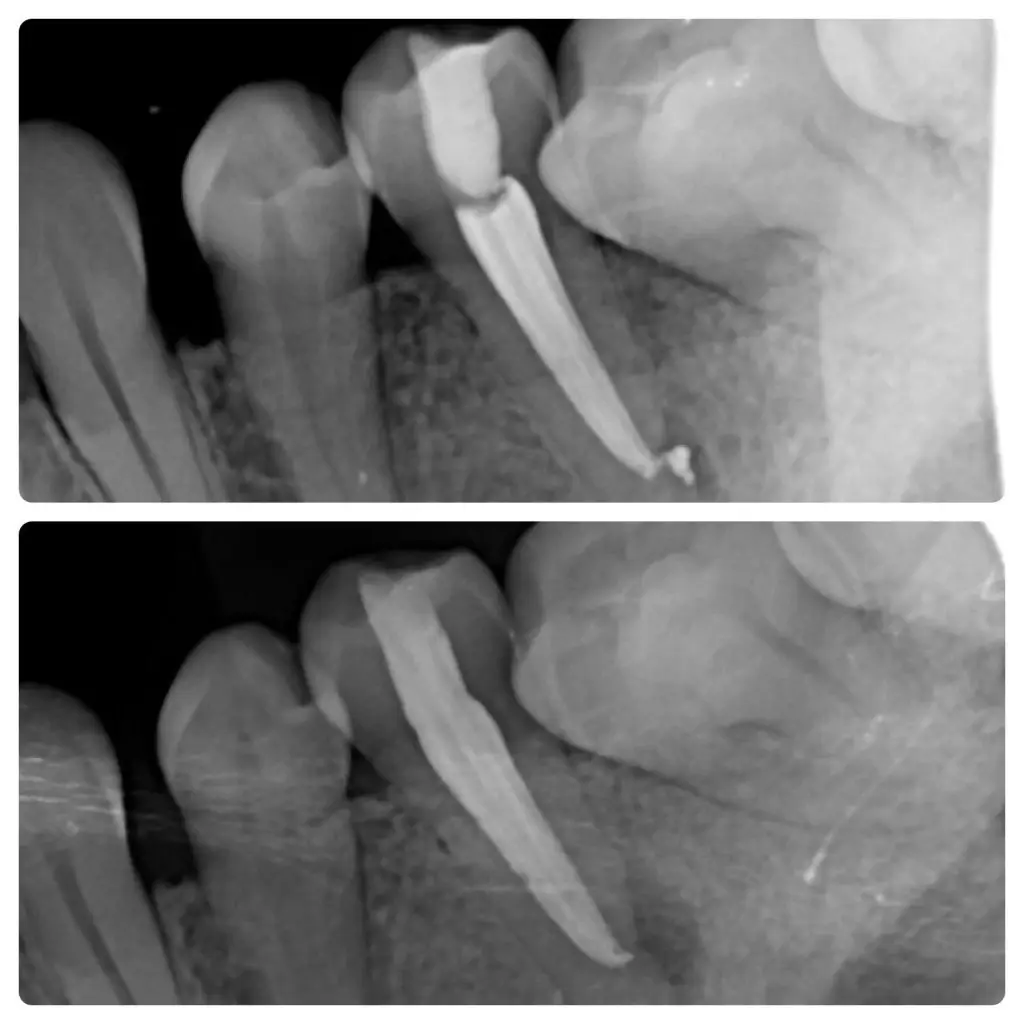

Gyökér tömés

A két kép 15 hónap különbséggel készült, az egyik a gyökértömés végén, a másik pedig egy kontroll vizsgálaton.

Ciszta mérete látványosan csökkent, majdnem teljesen elmúlt, a páciens panaszmentes 🙂